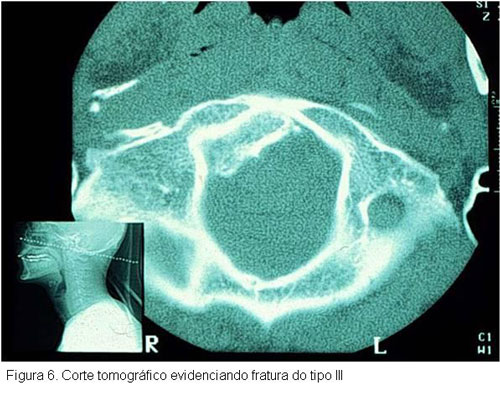

As fraturas de côndilo occipital são de difícil diagnóstico, dada a inespecificidade de seu quadro clínico. É extremamente difícil a sua visualização com as técnicas radiográficas convencionais, sendo necessária a utilização de métodos de diagnóstico por imagem mais sofisticados para seu reconhecimento. Entre estes métodos destaca-se a TC, sendo que esta permite a reconstrução das imagens nos planos sagital e coronal, bem como a reconstrução tridimensional.

A transição occipitocervical deve ser avaliada com extrema atenção, especialmente nos pacientes que apresentam traumatismos de face e crânio associados (Figura 6).